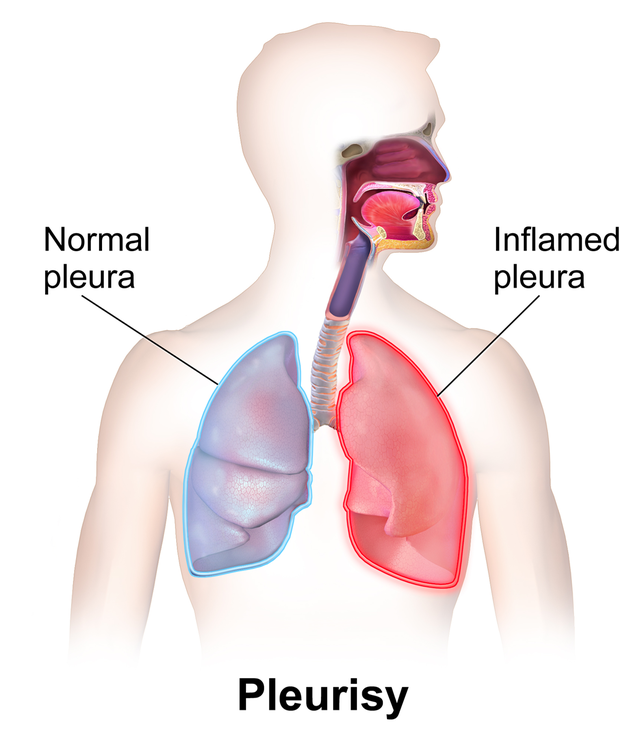

pleuritic pain– is caused during pleurisy, a condition of inflamed pleura caused by a variety of virus or bacterial or other illnesses that travels to the pleurae. The pleuritic chest pain can be defined as a sharp pains that gets worse during inspiration or expiration. Apart from the bacterial or viral infections, pleurisy can also be caused by autoimmune diseases (lupus), pleural disease (i.e., mesothelioma), chest trauma, sickle cell disease, IBD, pulmonary embolism and certain medications etc. (can make an image using bio-render)

friction rub – also known as pleural friction rub, is an involuntary breath sound resulting from the movement of inflamed and swollen pleural surfaces against each other. It can usually better heard during lung auscultation.